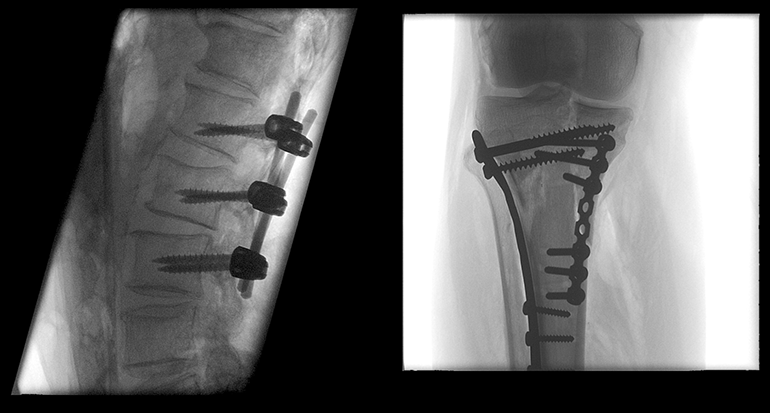

旗下的PLX7200型移动式三维C型臂等产品在市场获得了良好口碑,能够提供术中3D成像,适用于骨科、外科、矫形外科、泌尿外科、脊柱外科、腹部外科、疼痛科、消化科、妇科及手术室等,大幅度拓宽骨科手术范围,提高诊治水准。支持骨组织活检、脊柱椎弓根螺钉植入术、长管状骨髓内钉固定术、及适合采用螺钉固定的手、足骨折手术等骨科、创伤科复杂诊治。